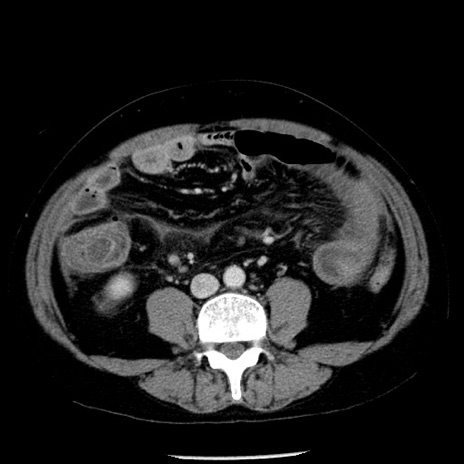

症例29(横断像)

【症例】40歳代男性

【現病歴】2日前から胃痛あり。徐々に周期的な激痛に変化した。本日になっても激痛があるため受診。

【身体所見】意識清明、BT 38-39℃台あり、腹部:膨満、やや硬、右下腹部に圧痛あり。

【データ】WBC 8500、CRP 23.26